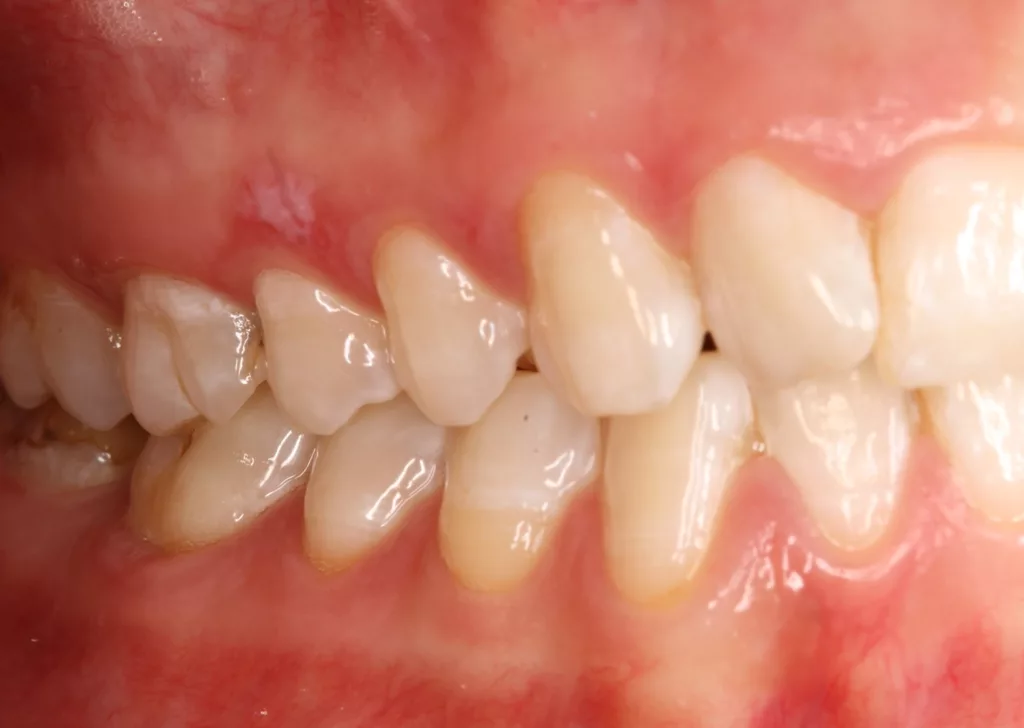

![Abb. 3a: Klinische Dokumentation einer 24-jährigen Patientin mit einer weit fortgeschrittenen lokalen parodontalen Destruktion, die mit großer Wahrscheinlichkeit durch ein Zungenpiercing hervorgerufen wurde [10]. Mit Ausnahme der Symptomatik im Unterkiefer-Frontzahnbereich wies die Patientin flache Sondierungstiefen und einzelne Regionen mit Gingivitis auf. Die Zähne reagierten positiv auf eine Sensibilitätsprobe mit Kältespray. Das Piercing war zum Zeitpunkt der Vorstellung in der Klinik bereits nicht mehr im Mund. Es wurde eine stufenweise systematische parodontale Therapie eingeleitet. Die verbliebenen und nahezu unveränderten erhöhten Son¬dierungstiefen wurden einem parodontal-chirurgischen Eingriff mit zusätzlichen, die Regenera¬tion fördernden Maßnahmen (Straumann Emdogain, Straumann, Basel, Schweiz) unterzogen. Es wurde die für diese Operationen empfohlene Schnittführung im Sinne eines Papillenerhaltungs¬lappens angewendet. Der nach der Degranulierung mit Hand- und Ultraschallinstrumenten sicht¬bare knöcherne Defekt wies eine ungünstige Morphologie für die Regeneration auf. Ein primärer Wundverschluss wurde dennoch erzielt. Diese Ansätze blieben letztendlich erfolglos und der Zahn 41 ging verloren (parodontologische Therapie gemeinsam mit Dr. L. Büttel, Basel, Schweiz).](https://dentalwelt.spitta.de/wp-content/uploads/2025/07/Abb-3a-1024x684.webp)

![Abb. 3b: Klinische Dokumentation einer 24-jährigen Patientin mit einer weit fortgeschrittenen lokalen parodontalen Destruktion, die mit großer Wahrscheinlichkeit durch ein Zungenpiercing hervorgerufen wurde [10]. Mit Ausnahme der Symptomatik im Unterkiefer-Frontzahnbereich wies die Patientin flache Sondierungstiefen und einzelne Regionen mit Gingivitis auf. Die Zähne reagierten positiv auf eine Sensibilitätsprobe mit Kältespray. Das Piercing war zum Zeitpunkt der Vorstellung in der Klinik bereits nicht mehr im Mund. Es wurde eine stufenweise systematische parodontale Therapie eingeleitet. Die verbliebenen und nahezu unveränderten erhöhten Son¬dierungstiefen wurden einem parodontal-chirurgischen Eingriff mit zusätzlichen, die Regenera¬tion fördernden Maßnahmen (Straumann Emdogain, Straumann, Basel, Schweiz) unterzogen. Es wurde die für diese Operationen empfohlene Schnittführung im Sinne eines Papillenerhaltungs¬lappens angewendet. Der nach der Degranulierung mit Hand- und Ultraschallinstrumenten sicht¬bare knöcherne Defekt wies eine ungünstige Morphologie für die Regeneration auf. Ein primärer Wundverschluss wurde dennoch erzielt. Diese Ansätze blieben letztendlich erfolglos und der Zahn 41 ging verloren (parodontologische Therapie gemeinsam mit Dr. L. Büttel, Basel, Schweiz).](https://dentalwelt.spitta.de/wp-content/uploads/2025/07/Abb-3b-1024x684.webp)

![Abb. 3c: Klinische Dokumentation einer 24-jährigen Patientin mit einer weit fortgeschrittenen lokalen parodontalen Destruktion, die mit großer Wahrscheinlichkeit durch ein Zungenpiercing hervorgerufen wurde [10]. Mit Ausnahme der Symptomatik im Unterkiefer-Frontzahnbereich wies die Patientin flache Sondierungstiefen und einzelne Regionen mit Gingivitis auf. Die Zähne reagierten positiv auf eine Sensibilitätsprobe mit Kältespray. Das Piercing war zum Zeitpunkt der Vorstellung in der Klinik bereits nicht mehr im Mund. Es wurde eine stufenweise systematische parodontale Therapie eingeleitet. Die verbliebenen und nahezu unveränderten erhöhten Son¬dierungstiefen wurden einem parodontal-chirurgischen Eingriff mit zusätzlichen, die Regenera¬tion fördernden Maßnahmen (Straumann Emdogain, Straumann, Basel, Schweiz) unterzogen. Es wurde die für diese Operationen empfohlene Schnittführung im Sinne eines Papillenerhaltungs¬lappens angewendet. Der nach der Degranulierung mit Hand- und Ultraschallinstrumenten sicht¬bare knöcherne Defekt wies eine ungünstige Morphologie für die Regeneration auf. Ein primärer Wundverschluss wurde dennoch erzielt. Diese Ansätze blieben letztendlich erfolglos und der Zahn 41 ging verloren (parodontologische Therapie gemeinsam mit Dr. L. Büttel, Basel, Schweiz).](https://dentalwelt.spitta.de/wp-content/uploads/2025/07/Abb-3c-1024x722.webp)

![Abb. 3d: Klinische Dokumentation einer 24-jährigen Patientin mit einer weit fortgeschrittenen lokalen parodontalen Destruktion, die mit großer Wahrscheinlichkeit durch ein Zungenpiercing hervorgerufen wurde [10]. Mit Ausnahme der Symptomatik im Unterkiefer-Frontzahnbereich wies die Patientin flache Sondierungstiefen und einzelne Regionen mit Gingivitis auf. Die Zähne reagierten positiv auf eine Sensibilitätsprobe mit Kältespray. Das Piercing war zum Zeitpunkt der Vorstellung in der Klinik bereits nicht mehr im Mund. Es wurde eine stufenweise systematische parodontale Therapie eingeleitet. Die verbliebenen und nahezu unveränderten erhöhten Son¬dierungstiefen wurden einem parodontal-chirurgischen Eingriff mit zusätzlichen, die Regenera¬tion fördernden Maßnahmen (Straumann Emdogain, Straumann, Basel, Schweiz) unterzogen. Es wurde die für diese Operationen empfohlene Schnittführung im Sinne eines Papillenerhaltungs¬lappens angewendet. Der nach der Degranulierung mit Hand- und Ultraschallinstrumenten sicht¬bare knöcherne Defekt wies eine ungünstige Morphologie für die Regeneration auf. Ein primärer Wundverschluss wurde dennoch erzielt. Diese Ansätze blieben letztendlich erfolglos und der Zahn 41 ging verloren (parodontologische Therapie gemeinsam mit Dr. L. Büttel, Basel, Schweiz).](https://dentalwelt.spitta.de/wp-content/uploads/2025/07/Abb-3d-1024x665.webp)

Wir sind vor mittlerweile 17 Jahren erstmals mit der Frage etwaiger Auswirkungen oraler Piercings auf den Zahnhalteapparat konfrontiert worden [10]. Eine damals 24-jährige Patientin stellte sich mit einem ungewöhnlichen Befund vor (Abb. 3a bis d). Bei sonst parodontal unauffälligen Verhältnissen mit Sondierungstiefen zwischen 2 und 3 mm, reichten die Sondierungstiefen an den Schneidezähnen im Unterkiefer bis 12 mm. Zahn 41 schmerzte und wies eine erhöhte Lockerung von Grad 2 auf. Bukkal war zudem eine Fistel mit Pusentleerung zu detektieren. Die Patientin war allgemeinmedizinisch gesund, rauchte nicht und hatte auch keinen Diabetes mellitus. Eine familiäre Prädisposition für parodontale Erkrankungen ließ sich anamnestisch nicht konstruieren. Die Mundhygiene war zwar nicht perfekt, stand aber auch in keinem Verhältnis zu ihrem dramatischen lokalen parodontalen Befund. Im Rahmen der anamnestischen Befragung, fokussiert auf ungewöhnliche Habits, berichtete die Patientin, bis vor kurzem ein Zungenpiercing getragen zu haben, dieses aber vor ca. sechs Monaten entfernt zu haben. Die Piercing-Tragedauer betrug etwa drei Jahre.

In der Gesamtschau der zusammengetragenen Daten und unter Berücksichtigung der in medizinischen Datenbanken aufgefundenen einzelnen Fallbeschreibungen erschien uns die wahrscheinlichste Ursache für den vorliegenden Befund tatsächlich das Zungenpiercing zu sein [11]. Die parodontale nicht-chirurgische, wie auch die chirurgisch-regenerative Therapie waren nicht erfolgreich und die Patientin verlor den stark kompromittierten Unterkiefer-Frontzahn. Seit dieser Zeit beschäftigen wir uns intensiver mit diesem Thema. So begannen wir mit der Sammlung und Erfassung der klinischen Parameter bei Patienten/-innen, die ein orales Piercing tragen oder einst trugen. Die Ergebnisse wurden zunächst im Rahmen einer Masterarbeit ausgewertet, als Posterbeitrag bei der Europerio 9 in Amsterdam veröffentlicht und später dann als Manuskript publiziert [10,12].